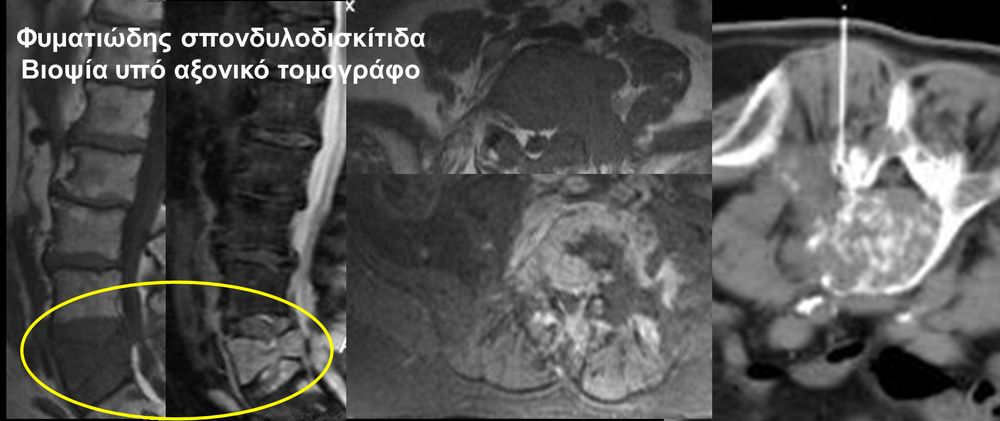

Η οστική βιοψία και η βιοψία όγκων μαλακών μορίων χρησιμοποιείται για την ιστολογική διάγνωση αλλοιώσεων (καλοήθων - κακοήθων / πρωτοπαθών ή μεταστατικών) ή για τη λήψη υλικού προς καλλιέργεια ώστε να αναδειχθεί το μικρόβιο που προκαλεί τη λοίμωξη του μυοσκελετικού συστηματος (πχ σπονδυλοδισκίτιδα). Η βιοψία υπό συνεχή απεικονιστική καθοδήγηση συμβάλλει στην υψηλή ακρίβεια τοποθέτησης της βελόνης εντός της βλάβης με ασφαλή προσπέλαση. Η χρήση σύγχρονων ομοαξονικών συστημάτων βιοψίας (coaxialtechnique) επιτρέπει την λήψη πολλαπλών δειγμάτων με μια μόνο παρακέντηση.